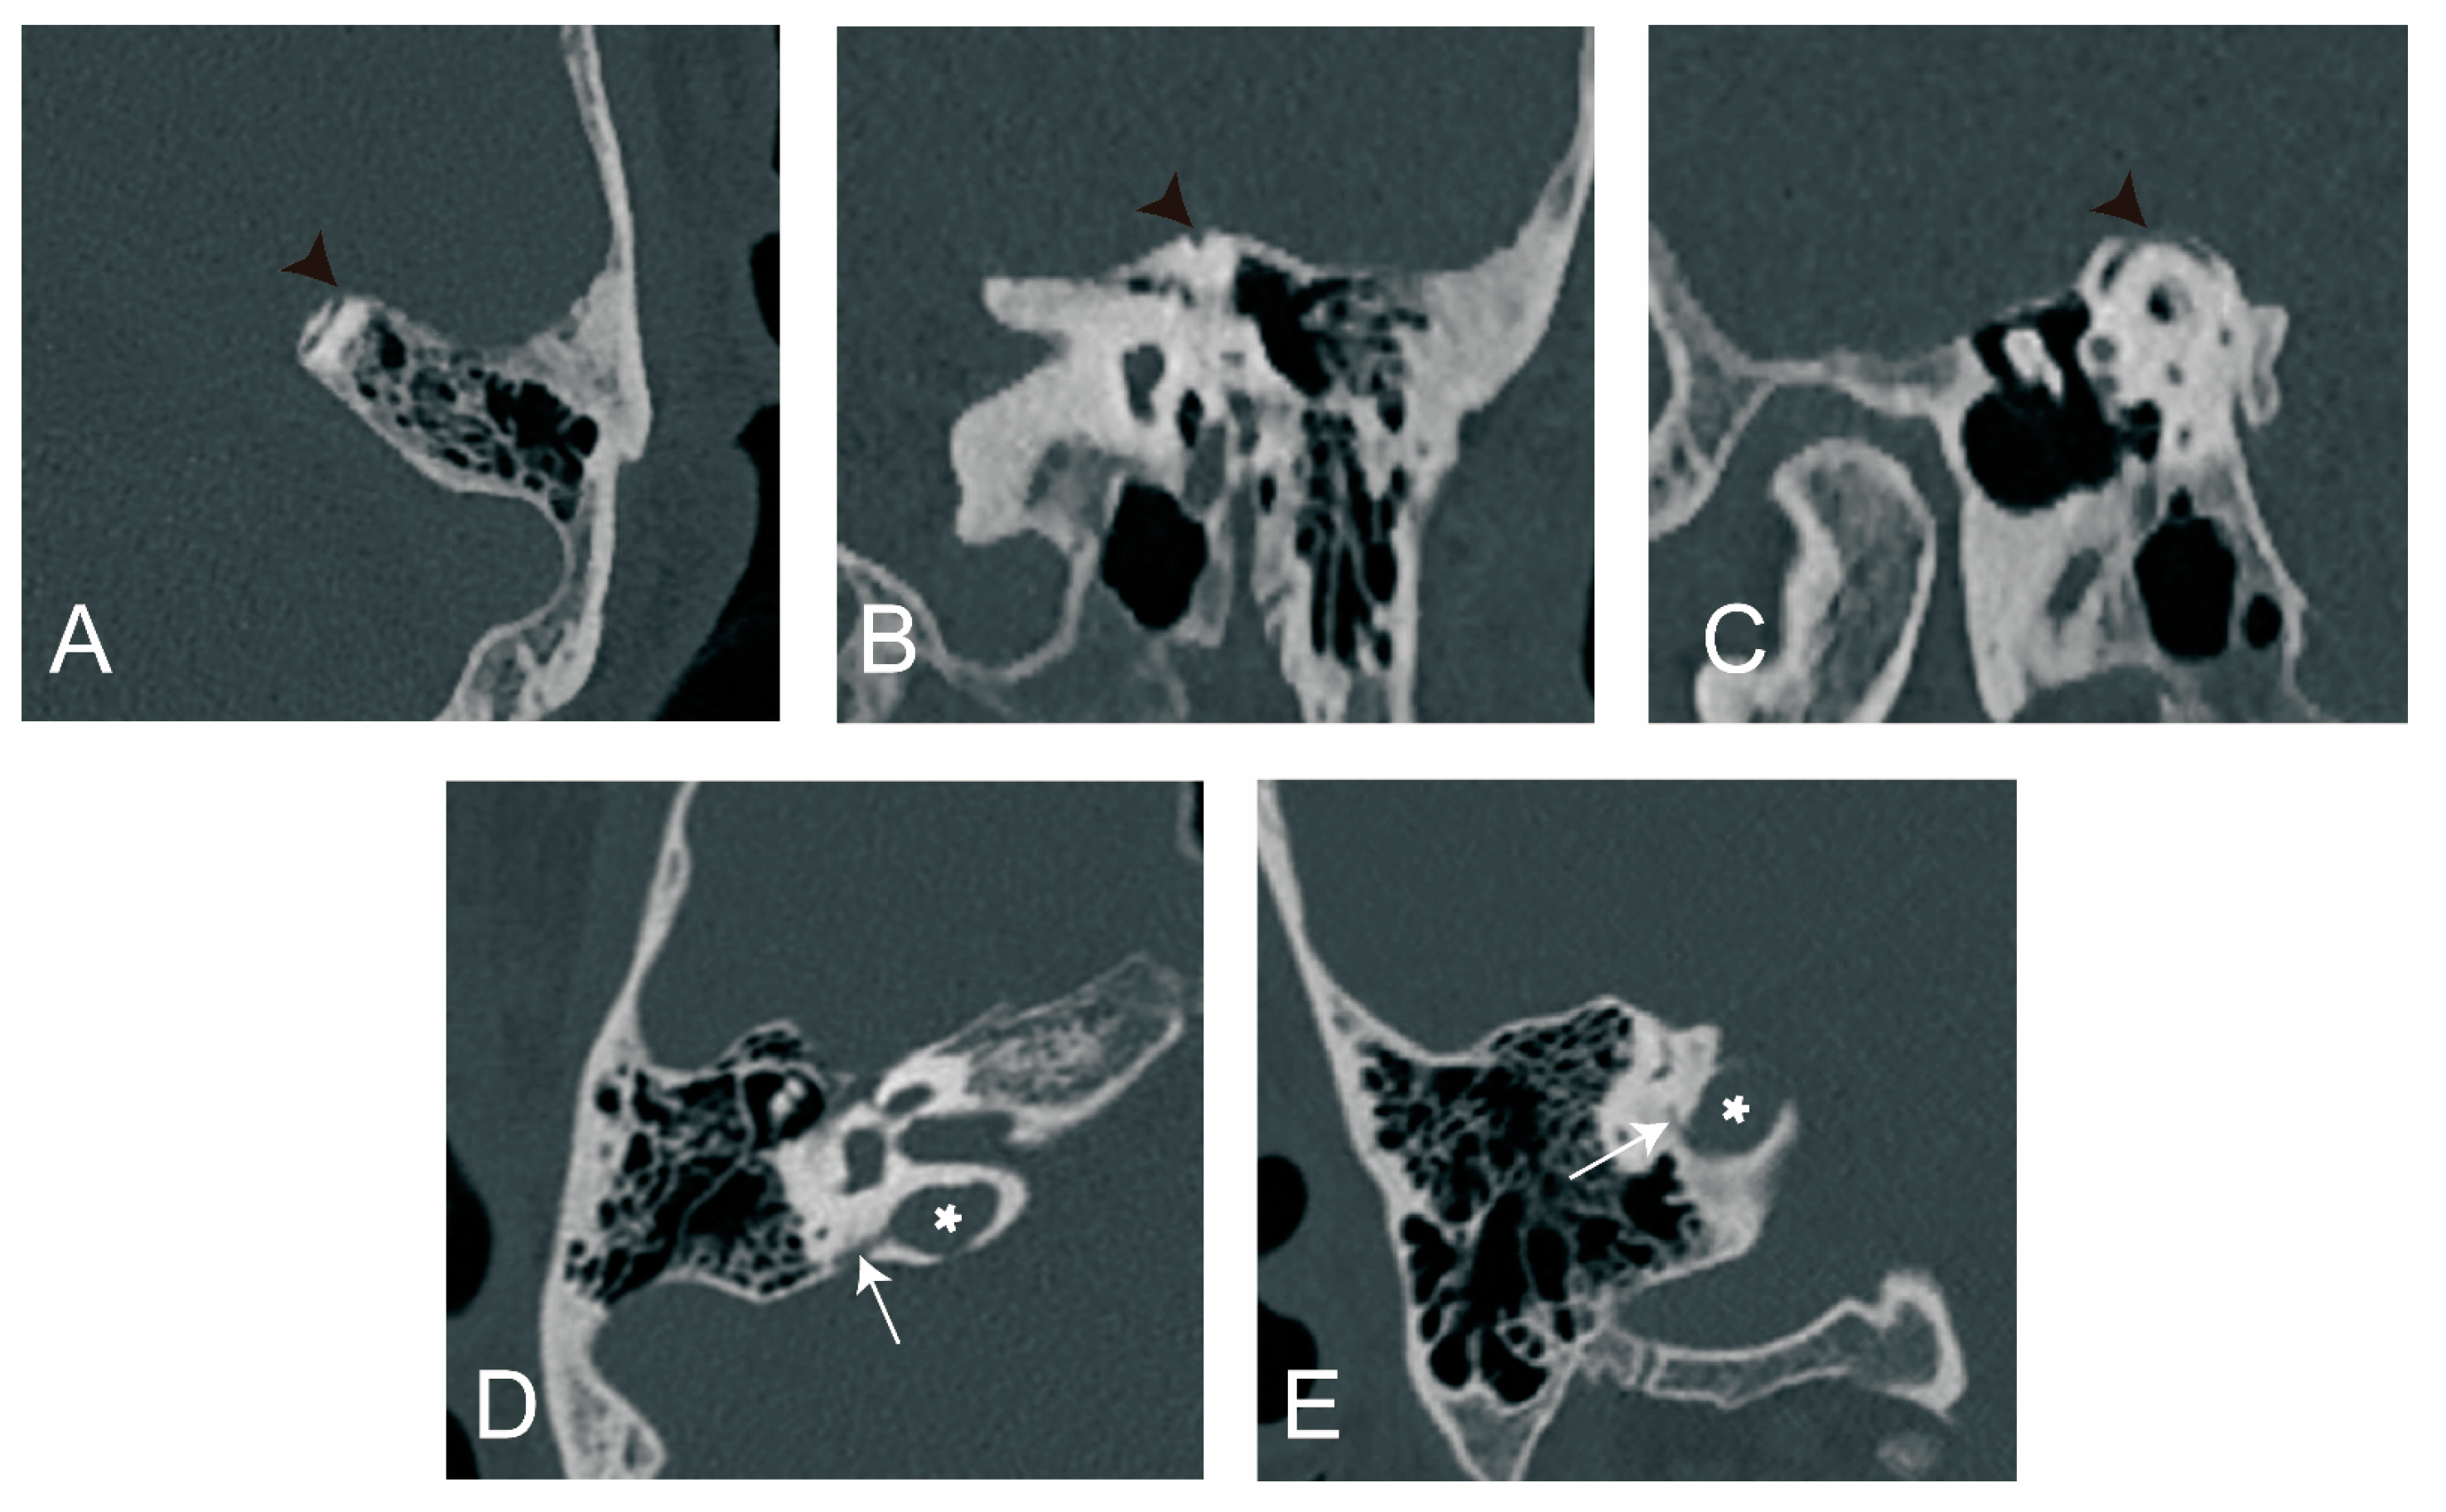

3.2.4. The Relationship between ATVA and Otic Capsule Dehiscence

4.2.4. The Relationship between ATVA and Otic Capsule Dehiscence

2.2.2. Radiological Measurement